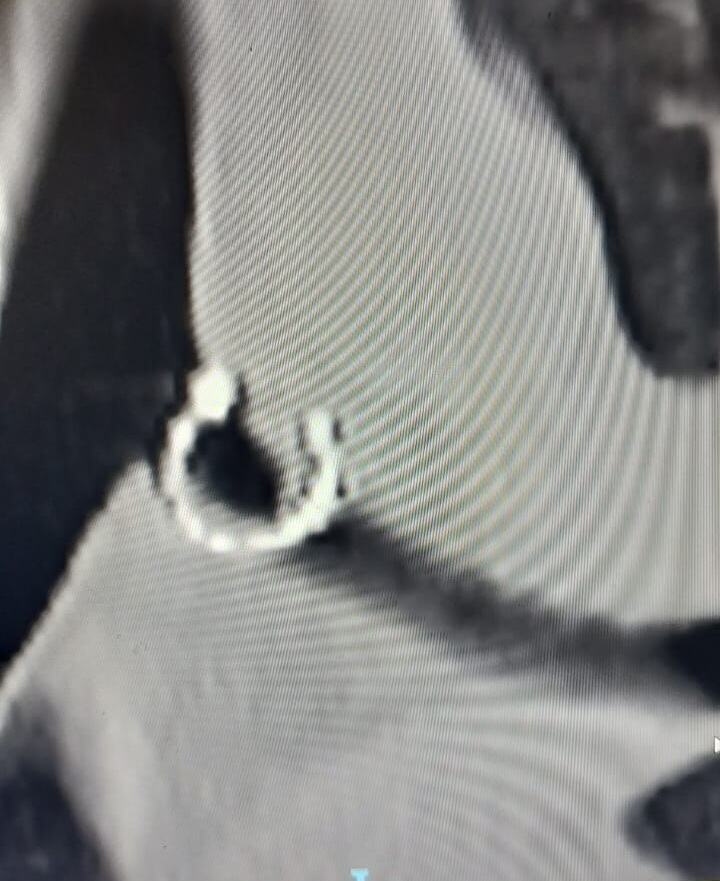

Mesec dana sam uporno kašljala: Lekari nisu mogli da veruju šta su mi pronašli u plućima, 0,5 milimetara od aorte

profimedia-1089210772.jpg

2 / 4

Jam Press / Jam Press / Profimedia